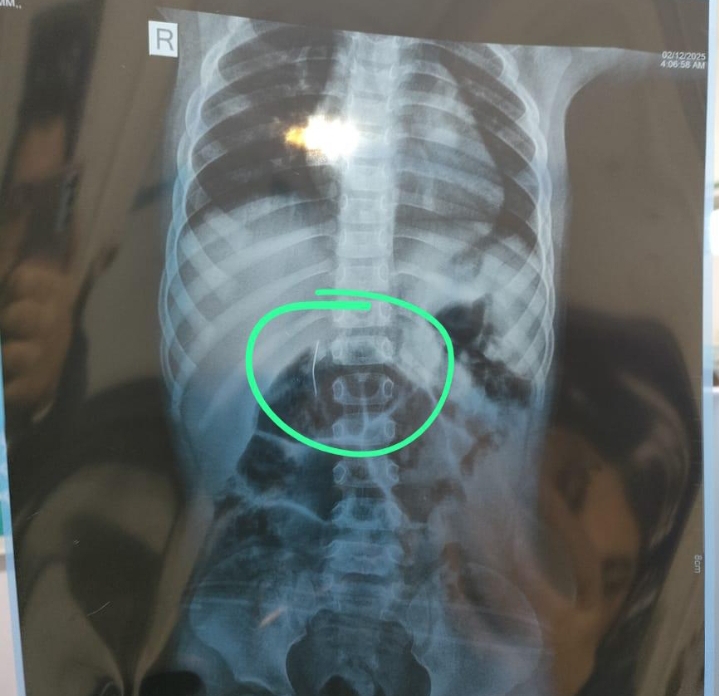

وأشار وكيل الوزارة إلى أن الفريق الطبي نجح أولًا في استخراج دبوس معدني مدبب من طفلة كانت معرضة لخطر ثقب المريء أو المعدة، ثم تمكن من إخراج قطعة مغناطيسية خطرة من طفل آخر قبل أن تتسبب في التصاق أجزاء من الأمعاء أو حدوث انسداد، كما قام الفريق الطبي باستخراج بطارية معدنية من طفل ثالث قبل أن تؤدي إلى تآكل شديد بجدار المريء، مؤكدًا أن التدخل السريع والمهارة الدقيقة للفريق الطبي كانا عاملين حاسمين في إنقاذ حياة الأطفال الثلاثة.

ولفت الدكتور البيلي إلى أن جميع العمليات أُجريت باستخدام المنظار ودون أي تدخل جراحي، ما سمح بخروج الأطفال بحالة صحية مستقرة تمامًا بعد الاطمئنان على سلامة أجهزتهم الداخلية، مشيدًا بكفاءة الفريق الطبي وقدرته على التعامل مع مثل هذه الحالات المعقدة في وقت قياسي، وباستخدام تقنيات متقدمة تتيح أعلى معدلات الأمان والدقة.